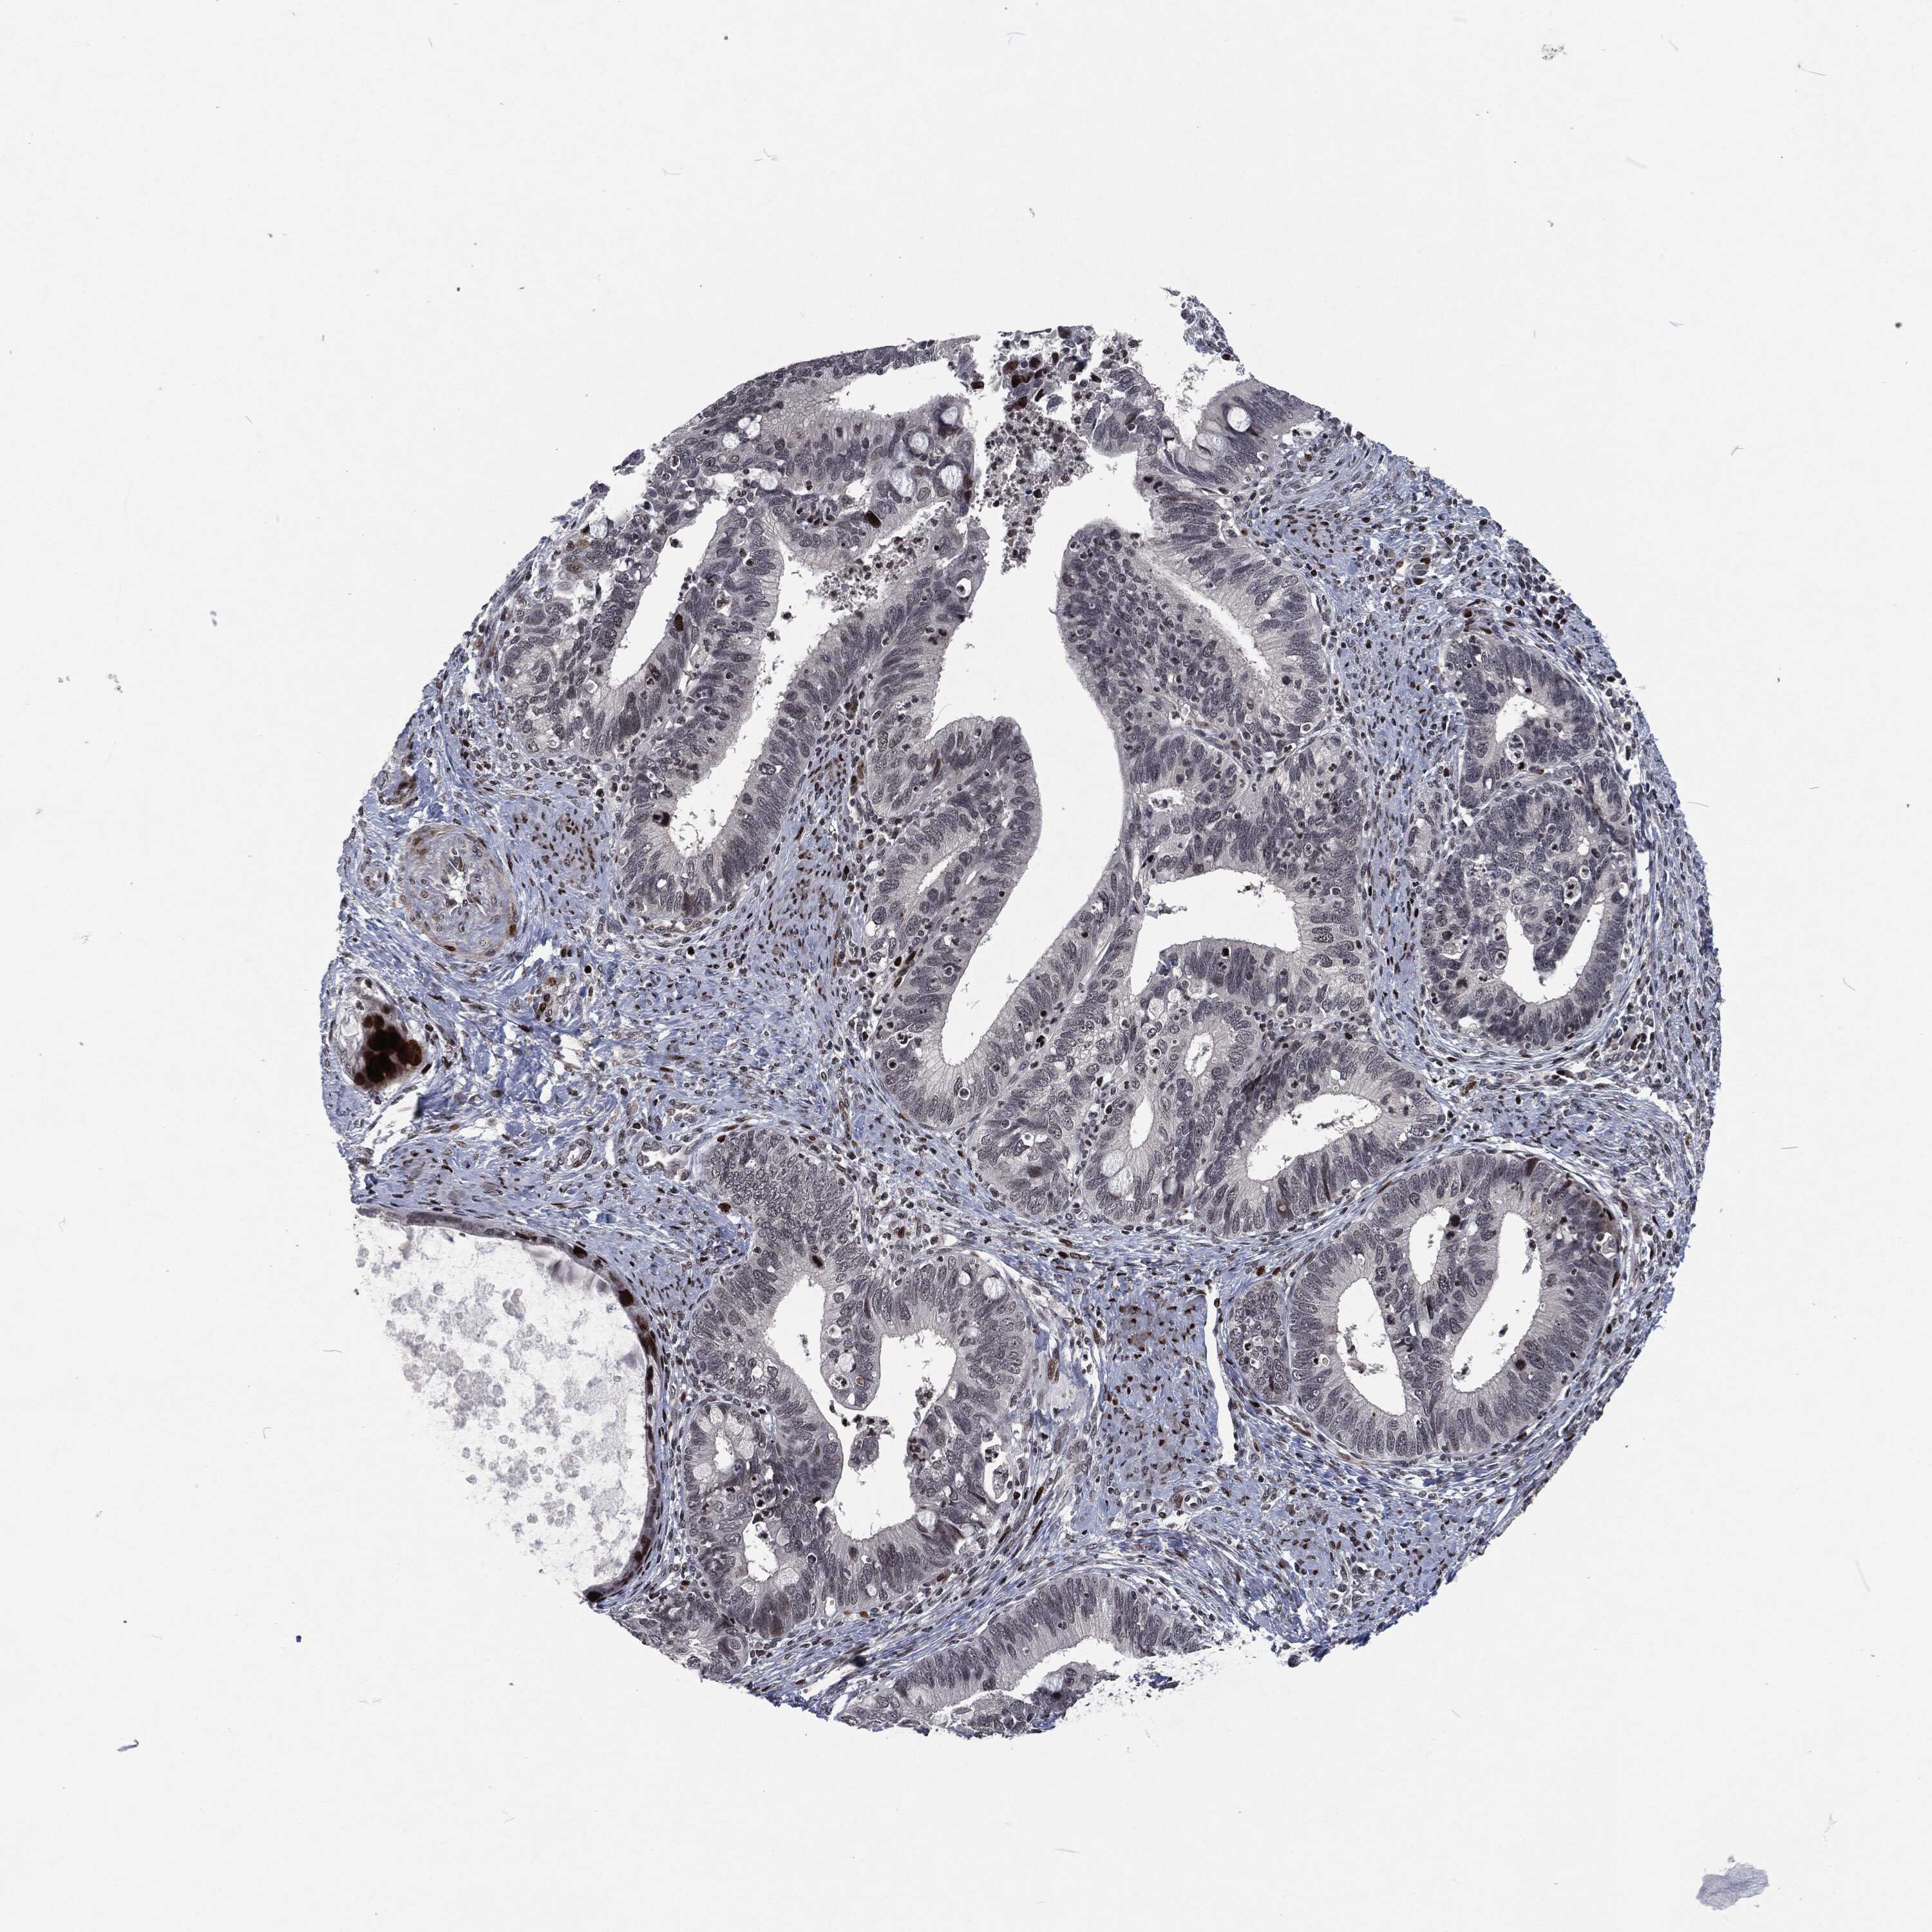

CERVICAL CANCER - Protein expressioni

A mouse-over function shows sample information and annotation data. Click on an image to view it in a full screen mode. Samples can be filtered based on level of antibody staining by selecting one or several of the following categories: high, medium, low and not detected. The assay and annotation is described here.

Note that samples used for immunohistochemistry by the Human Protein Atlas do not correspond to samples in the TCGA dataset.

Antibody stainingi

Antibody staining in the annotated cell types in the current human tissue is reported as not detected, low, medium, or high, based on conventional immunohistochemistry profiling in selected tissues. This score is based on the combination of the staining intensity and fraction of stained cells.

Each image is clickable and will lead to virtual microscopy that enables deeper exploration of all samples and also displays staining intensity scores, fraction scores and subcellular localization as well as patient and tissue information for each sample.

Adenocarcinoma, NOS

Squamous cell carcinoma, NOS